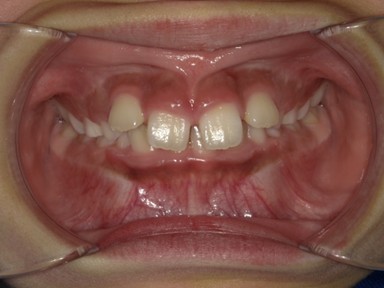

| 主訴 | 前歯が出ているので歯並びを良くしたい。 |

| 治療内容 | 使用装置:- マイオブレース(K1, K2, B1, K3) – 急速拡大装置 ・ワイヤー矯正:上顎前歯部(2-2)のみに2か月間使用 ・抜歯:なし |

| 治療費 | 550,000円(税込み) |

| 治療期間 | 2020年2月~2023年1月(永久歯列完成まで観察) |

| 治療回数 | 25回 |

| 想定されたリスク | 全額ワイヤー治療になる可能性とそれに伴う歯根吸収のリスクがありました。 |

かみ合わせが非常に深く、下顎の成長を妨げておりました。扁桃腺の肥大が一因として考えられたため切除の提案をしました。マイオブレースを中心に、短期間のワイヤー治療でかみ合わせも健康面も良好になったかと思います。